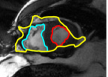

The problem above is a generalization of Horn & Schunck optical flow. Note that solving for the Horn & Schunck optical flow within each region separately does not lead to motions such that at the interface, they have equal normal components (see Figure 1), whereas the solution of (5) to be presented in subsequent sections does. Note that computing Horn & Schunck optical flow in each region requires boundary conditions (and typically they are chosen to be Neumann boundary conditions: and on ). Note that replacing these boundary conditions with the boundary constraint (6) does not specify a unique solution. Also, while Horn & Schunck optical flow computed on the whole domain naturally gives a globally smooth motion, which by default satisfies matching normals at the interface, this is not natural for the ventricles / myocardium, where different motions exist in the regions (see Figure 2), and the motions should not be smoothed across the regions.

![]() |

| image + boundary | global optical flow | our method | our method (motion decomp.) |